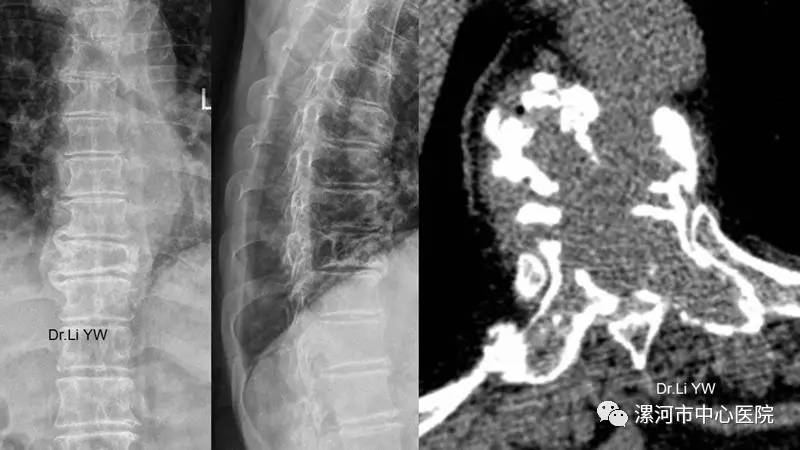

全市首例!把水泥装进袋子治疗脊柱转移癌-

800x450 - 42KB - JPEG